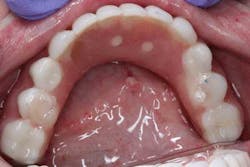

The maxillary arch was indexed first as there was support from the palate to reference position (anterior/posterior) (figure 20). Then the lower was put into position to gain proper vertical dimension and occlusion. It, too, was then indexed; both upper and lower were given to the lab technician to start the conversion process. Next, impression copings were placed (one arch at a time) and secured with paperclips; a full-arch PVS impression was taken and likewise sent to the lab (figures 21-23). Finally, after the conversion process was completed, the bridges were secured in place on the multiunit abutments, torqued to 15nCm, and covered. Bite was adjusted and follow-up care was arranged (figures 24-26).

Follow-up went well. Sara’s healing was satisfactory; she will continue with this long-term provisional that will eventually be replaced with a reinforced definitive restoration.